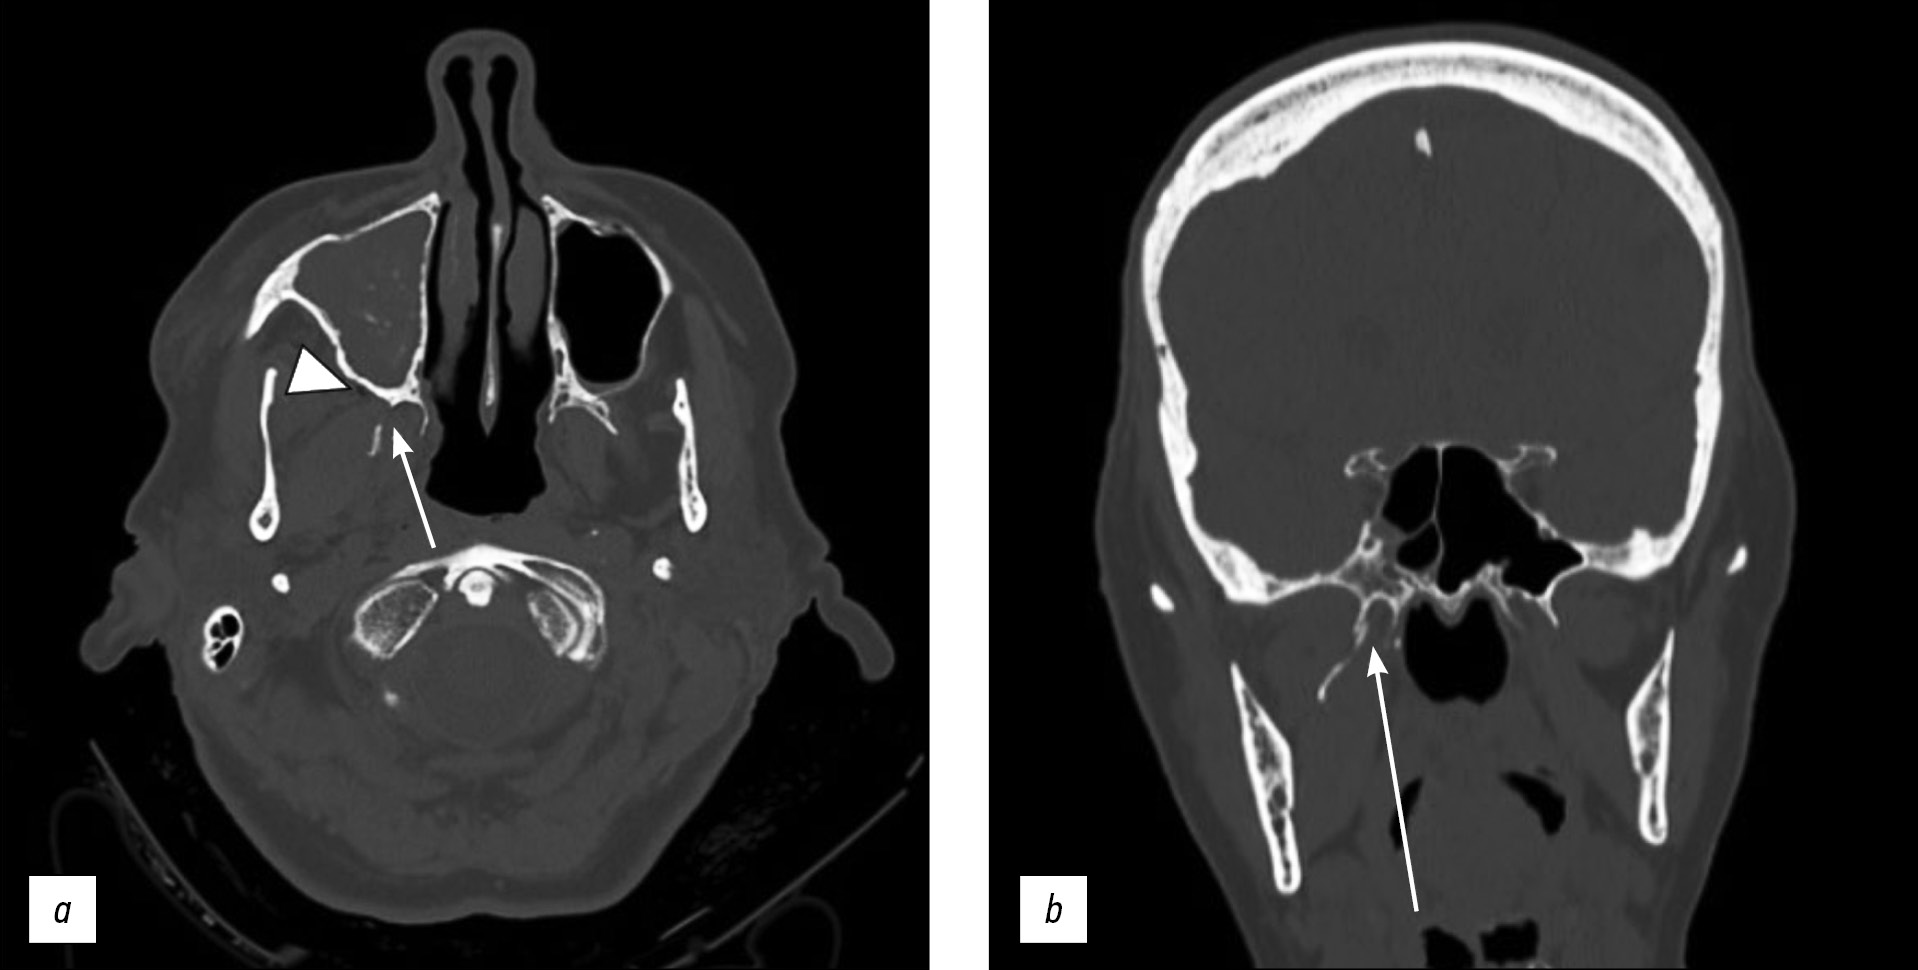

A computed tomography scan showed unilateral right pterygoid plate fracture with signs of emphysema in the ipsilateral masticatory space. The patient also had a fracture of the medial wall of the right maxillary sinus with hemosine, but no fractures of the skull base or theca. She was treated conservatively.